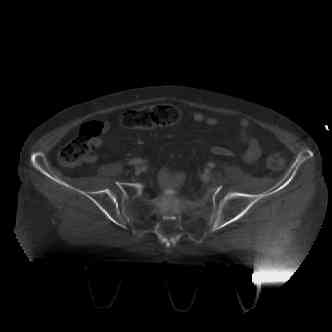

attached are images of a 70 year old female after peds versus car. her own car ran her over.

injuries are limited to the pelvis. left rami open and visible in a 10cm vertical laceration just lateral to left labia majora. wound is grossly clean. no vaginal and no urinary issues. CT scan shows widening of both SI joints anteriorly but I think this is vertically stable pattern.

pt treated that night with I/D and supra-acetabular frame to close the ring. consideration was given for SI screws bilateraly, but given time of night and other factors decision made not to proceed.

so the question is what next operatively if anything? concerns are infection, nonunion anteriorly and possible incompetence of the pelvic floor which may lead to prolapse issues. right rami are comminuted and plating may entail ilioinguinal approach to extend plate laterally to right iliac wing. retrograde screw up right rami is an option but I am not convinced it will add much. adding SI screws very doable, but major concern is restoring anterior ring. so far wound is clean and closed over a drain, and I have no plans to open it back up and wash again.

maintaining pelvic alignment in ex-fix in 70 yo female for any length of time may be challenging.

any thoughts? would anyone plate the pubic symphysis to close the gap and leave the more lateral rami fractures alone? the most recent pelvic case on this website involved pts with suprapubic catheters and antibiotic options including resorbable beads. I wonder how many people would plate and place antibiotic beads. thanks.

attached are several CT cuts. please let me know if you need more. the CT is pre-pelvic ex-fix placement.

Thank you.